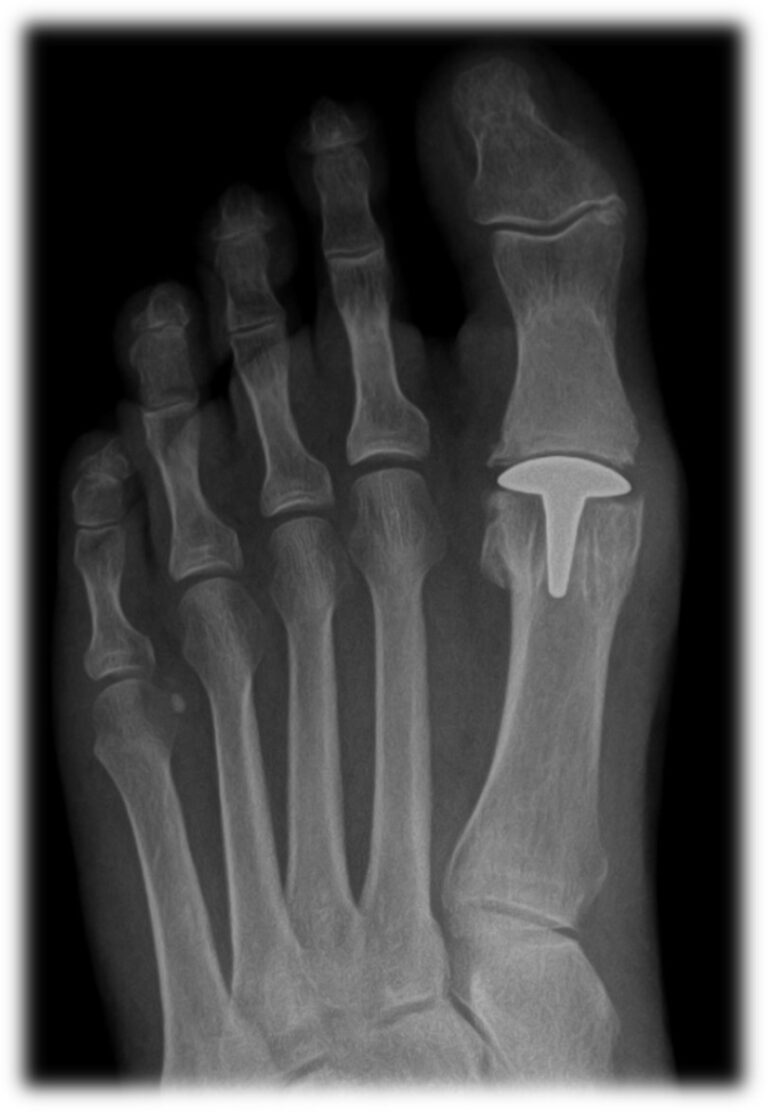

BioPro Hemi Toe Implant for Hallux Rigidus

From bioproimplants.com

BioPro Hemi Toe Implant for Hallux Rigidus Types Of Big Toe Joint Replacements Fixing the bones together (fusion) of the big toe joint (arthrodesis), is the most common surgery. • the damaged joint surfaces are removed and. What is arthritis of the big toe joint? With more advanced wear and tear and painful stiff toe other options are joint replacement or fusion of the big toe joint. Hallux rigidus, is arthritis (pain and. Types Of Big Toe Joint Replacements.